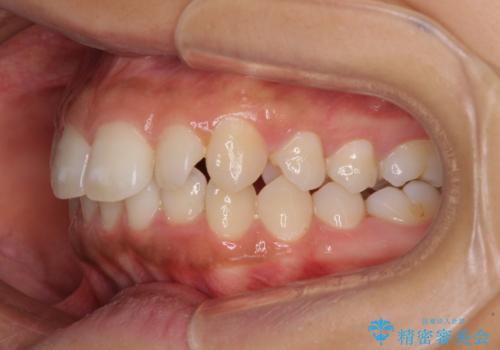

- 出っ歯で唇が閉じにくいとのことで来院された患者様です。

顎先に力を入れないと唇が閉じきれない口元であったので、上下左右の第一小臼歯4本を抜歯して、ワイヤー装置にて矯正治療を行うこととしました。

2年から2年半の治療期間を想定しており、予定通りの期間で無事に終了することができました。

唇や顎先に力を入れないなくてもスムーズに唇を閉じることができるようになりました。